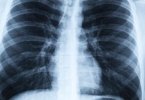

(3)其他感染或阻塞:肺结核、支气管扩张或异物阻塞也可能导致黄痰,应通过影像学检查(如胸片、CT)明确诊断,并采用针对性治疗方法。